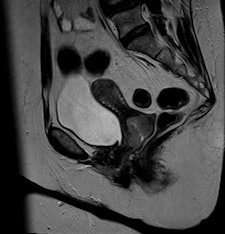

They found BLADE significantly (p < 0.0001) reduced motion and ghosting artifacts and showed improved conspicuity, but overall image quality did not differ significantly in the 47 patients who underwent sagittal BLADE and conventional TSE at 1.5-tesla after glucagon administration. In the majority of cases (53.2% versus 59.6%), radiologists preferred conventional TSE due to better image contrast and visibility of free pelvic fluid. Signal-to-noise ratio (SNR) and contrast-to-noise ratio (CNR) were significantly higher on conventional TSE.

"In our comparative study, the overall image contrast was reduced when using BLADE. This might be explained with the nonuniform T2-weighting along the width of the blade, i.e., the phase-encoding direction with contrast predominantly determined by low-frequency data as described by Pandit et al," Froehlich and colleagues wrote. "The reduced SNR and CNR in BLADE images occurred despite more frequent sampling of the k-space center. This was likely because the bandwidth in BLADE was twice as large as in conventional TSE (260 Hz per pixel in BLADE compared with 130 Hz per pixel in conventional TSE)."

"Indeed, conventional T2-weighted TSE provided a significantly better visibility of free pelvic fluid or cystic structures (i.e., a relatively higher effective T2 weighting) in numerous cases," the researchers noted.

BLADE improves anatomic depiction and image quality thanks to less movement artifact, but at the expense of CNR of cystic structures or visibility of free pelvic fluid.